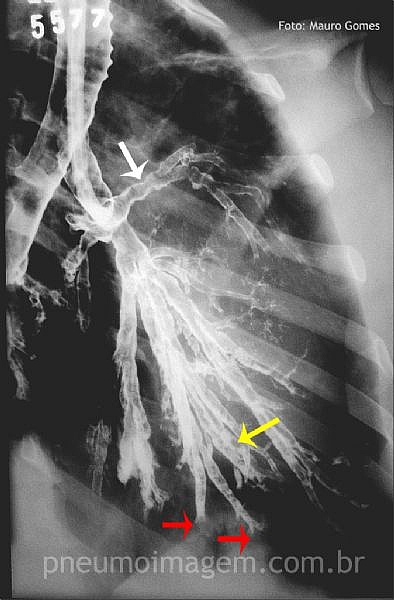

CASO CLÍNICO #35Você sabe o nome desse exame, sua indicação e o que as setas estão apontando? Deixe os seus comentários abaixo!

You know the name of this radiological examination, indications and that the arrows are pointing? Give your comments below!

O exame é BRONCOGRAFIA! Indicada ha anos atras para diagnostico de várias patologias pulmonares antes do advento da tomografia computadorzida! A seta ao meu ver mostra dilatações brônquicas=bronquiectasias!